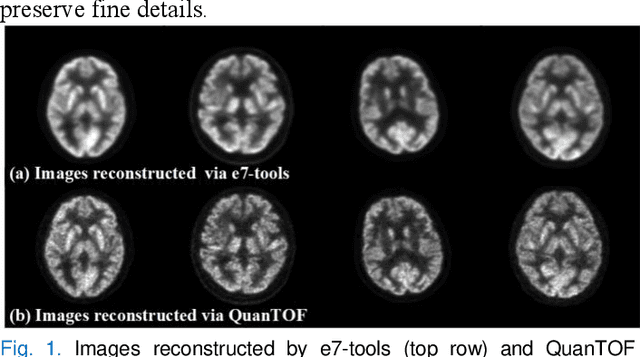

Abstract:Deep learning-based reconstruction of positron emission tomography(PET) data has gained increasing attention in recent years. While these methods achieve fast reconstruction,concerns remain regarding quantitative accuracy and the presence of artifacts,stemming from limited model interpretability,data driven dependence, and overfitting risks.These challenges have hindered clinical adoption.To address them,we propose a conditional diffusion model with posterior physical correction (PET-DPC) for PET image reconstruction. An innovative normalization procedure generates the input Geometric TOF Probabilistic Image (GTP-image),while physical information is incorporated during the diffusion sampling process to perform posterior scatter,attenuation,and random corrections. The model was trained and validated on 300 brain and 50 whole-body PET datasets,a physical phantom,and 20 simulated brain datasets. PET-DPC produced reconstructions closely aligned with fully corrected OSEM images,outperforming end-to-end deep learning models in quantitative metrics and,in some cases, surpassing traditional iterative methods. The model also generalized well to out-of-distribution(OOD) data. Compared to iterative methods,PET-DPC reduced reconstruction time by 50% for brain scans and 85% for whole-body scans. Ablation studies confirmed the critical role of posterior correction in implementing scatter and attenuation corrections,enhancing reconstruction accuracy. Experiments with physical phantoms further demonstrated PET-DPC's ability to preserve background uniformity and accurately reproduce tumor-to-background intensity ratios. Overall,these results highlight PET-DPC as a promising approach for rapid, quantitatively accurate PET reconstruction,with strong potential to improve clinical imaging workflows.